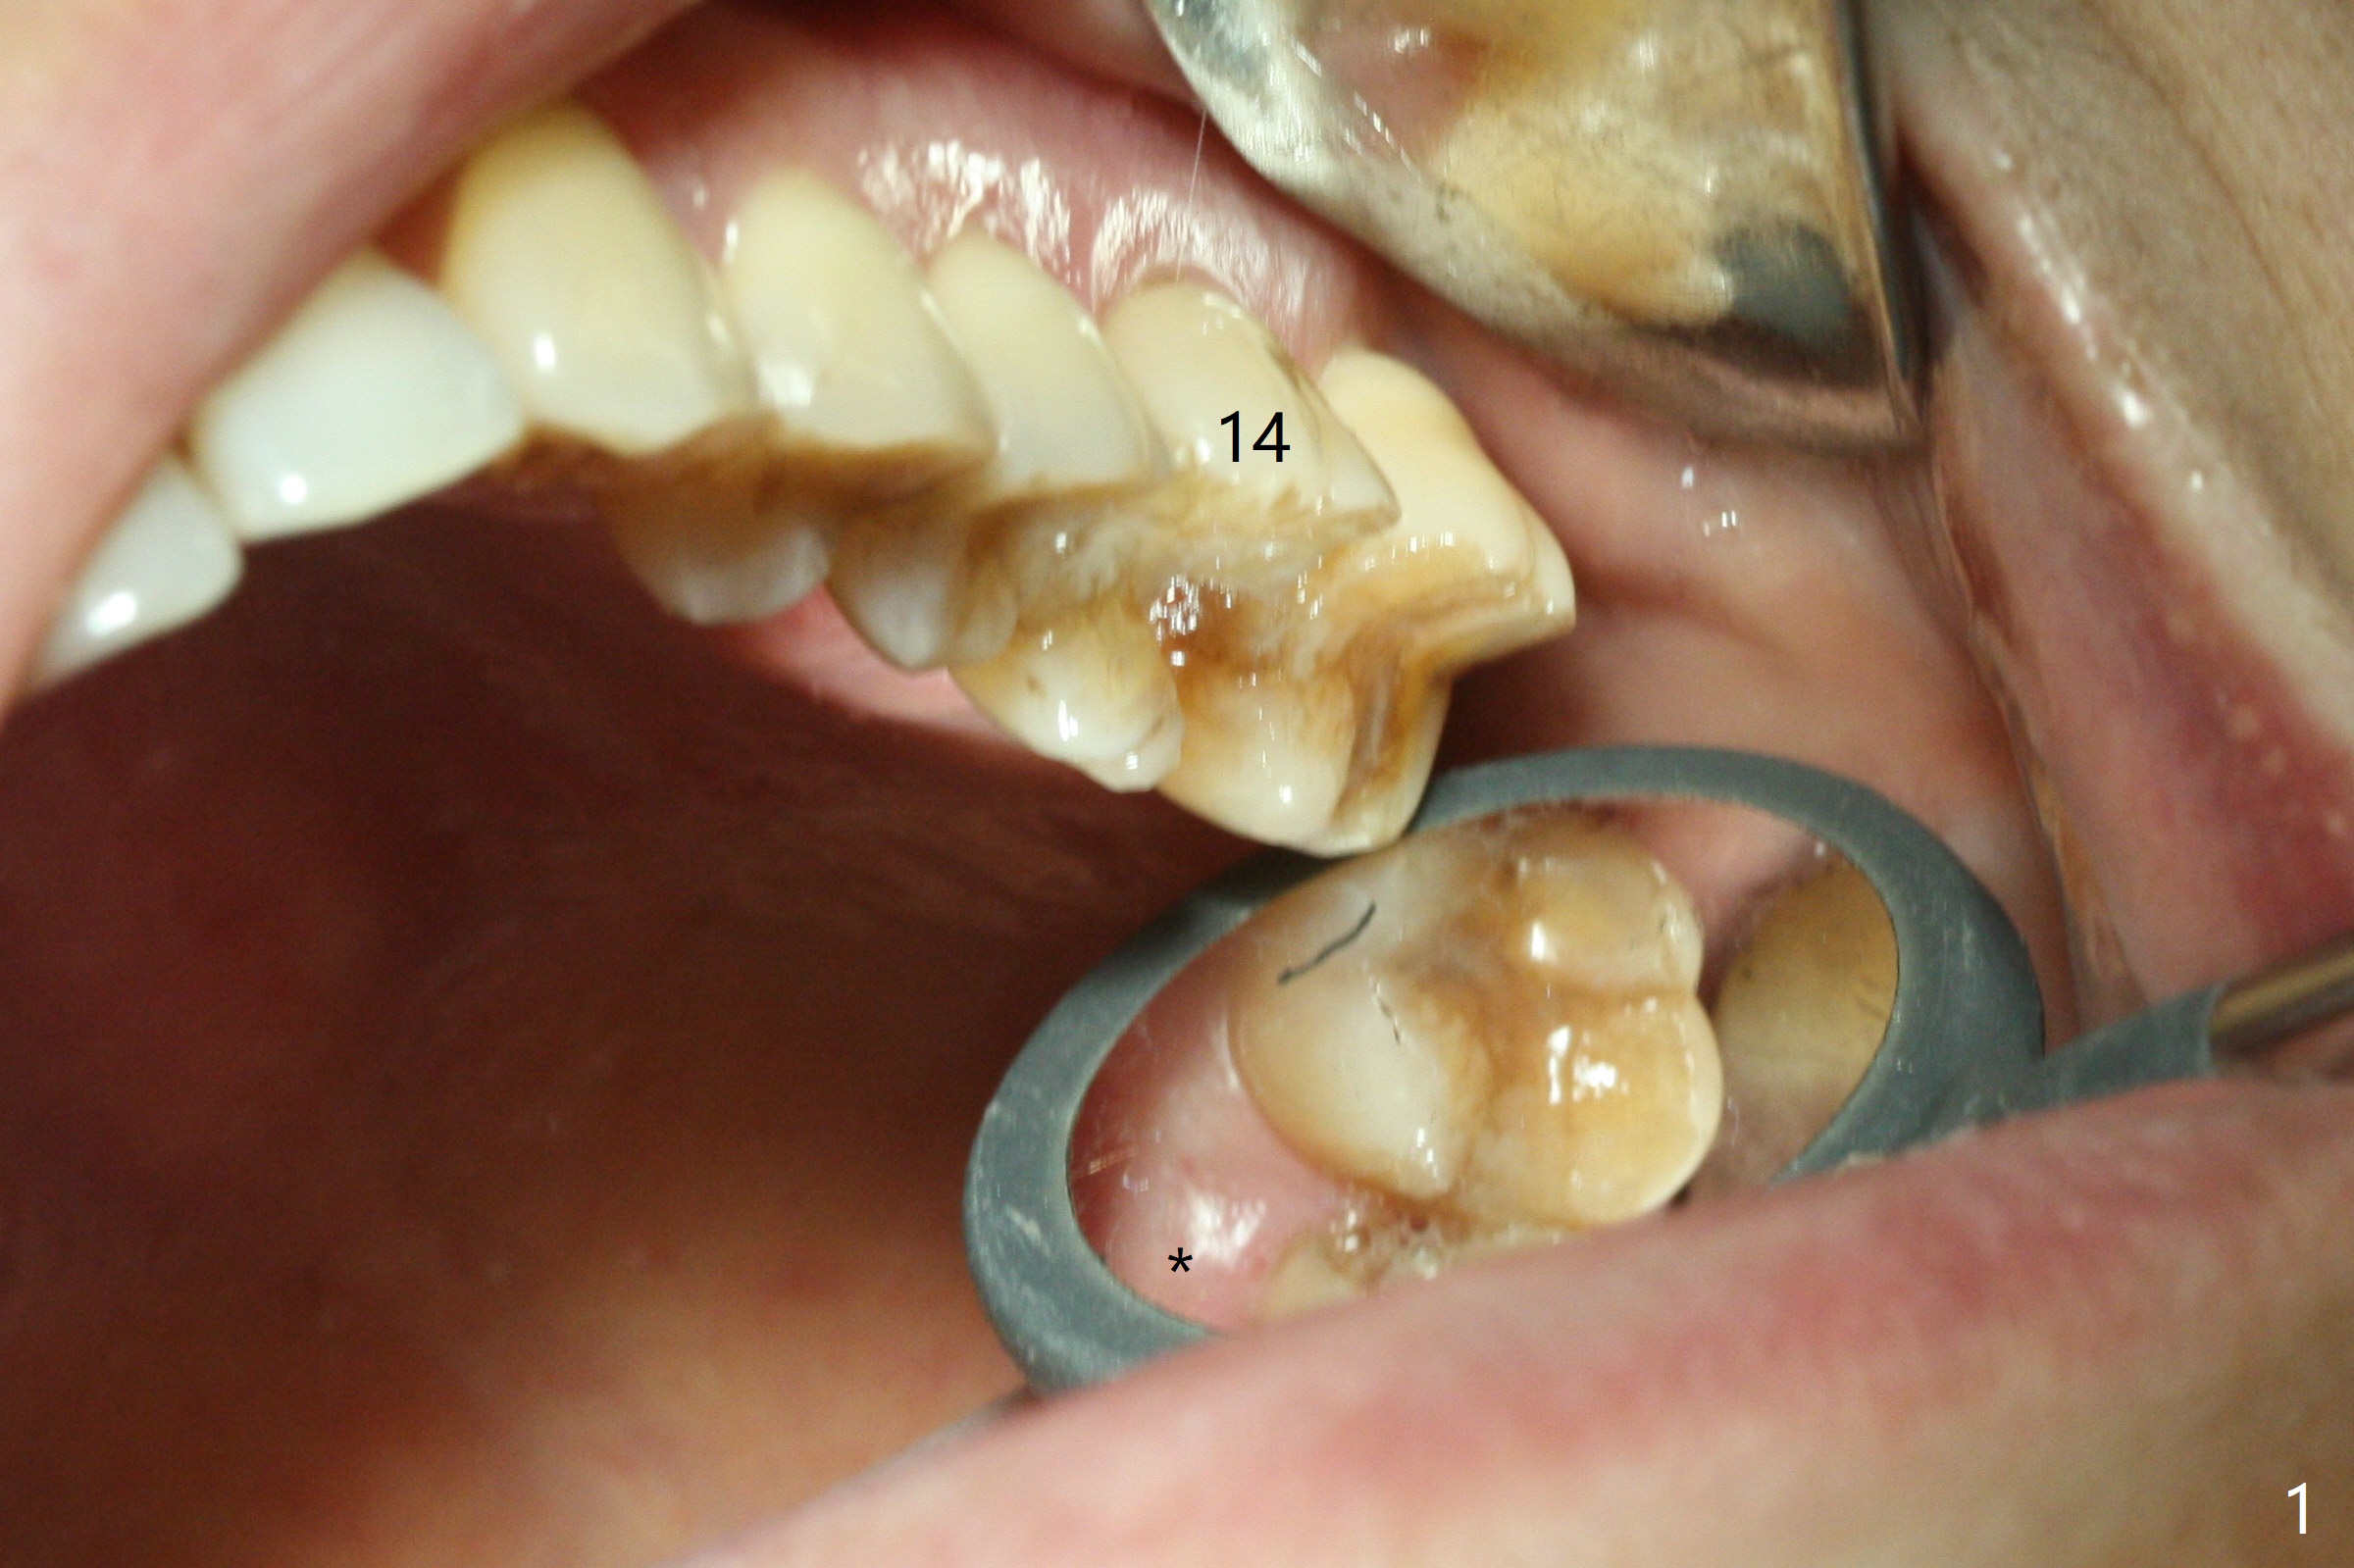

After extraction of the tooth #14 with palatal swelling (Fig.1 *), the septum (S in Fig.2) is found to be thin. Sequential osteotomy quickly deviates to the palatal socket. In spite of using Lindamann bur to remove the bone from the buccal portion of the osteotomy, the apical end of a 5x9 mm dummy implant slides into the palatal socket with the coronal end placed as buccal as possible for restoration (Fig.2 (poor trajectory)). Further use of Lindamann bur for buccal bone removal is not feasible, since the buccoapical portion of the osteotomy starts to be perforated with apparently intact sinus membrane. With insertion of Vanilla graft for sinus lift through the buccoapical portion of the osteotomy mentioned above, a 6x11 mm implant is placed with the same trajectory (Fig.2, <40 Ncm). With placement of a 6.5x4(3) mm abutment (off angle) and of Vanilla graft in the remaining sockets (Fig.2 *), periodontal dressing is applied. When the dressing is dislodged for the 2nd time (12 days postop with healing socket), an angled abutment 5x15 degree, 3 mm cuff, is placed and a provisional is fabricated. There is no sign of sinus infection. The provisional and angled abutment become loose without sinus infection 2 months postop. A 5.5x3 mm healing abutment is placed with light tenderness. If this case turns to be failure, do not stick an immediate implant from potentially infected socket into the sinus in the future. The socket appears to heal 11 months postop (Fig.4). Later a 5x4(3) mm abutment is placed for final restoration. The palatal margin is low. The abutment screw is loose <2 months post cementation, probably due to deep placement and poor trajectory (buccal). It becomes loose again 4 months later. Prior to retightening, a 6 mm profile drill is used. BW shows no bony interference (Fig.5 (opposing tooth occlusal wear; bruxism)), while PA shows the buccal bone, suggesting poor trajectory. The abutment is loose for the 3rd time 17 months post cementation. When the crown/abutment is removed, the hex is worn. After proximal reduction, the crown/abutment feels to be unable to be re-seated. When the crown is sectioned, the abutment itself is incompletely seated (Fig.7,8). The mesial crest appears to interfere with seating (Fig.8). When the 5.2x3 mm dummy abutment is seated, the buccal margin is subgingival, while the palatal one supragingival, suggesting the buccally tilted implant (guided surgery essential). A 4.5x4(4) mm pair abutment seems to be seated completely (Fig.9). The hex of the 5x4(3) mm abutment is worn, but the abutment seems to be able to be seated completely (Fig.11), although not so crisply (easily) as the unworn one clinically. Return to Upper Molar Immediate Implant, Prevent Molar Periimplantitis (Protocols, Table), Armaments Screw Xin Wei, DDS, PhD, MS 1st edition 06/26/2018, last revision 12/20/2020